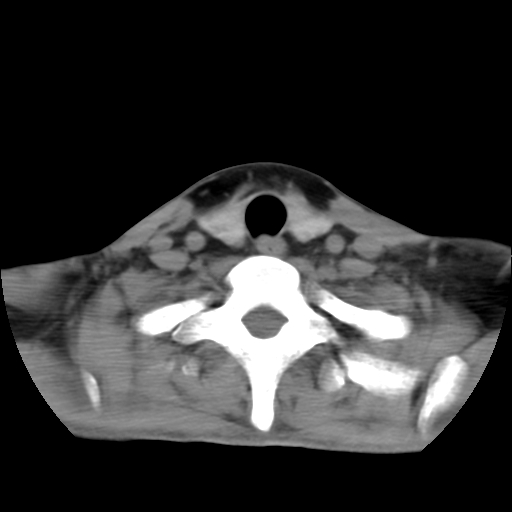

标题: CT24019:男,45岁,发现颈部肿物5个月。 [打印本页]

男,45岁,发现颈部肿物5个月,彩超示:双侧颈部及下颌部软组织增厚。

考虑双侧颈项部良性对称性脂肪增多症。